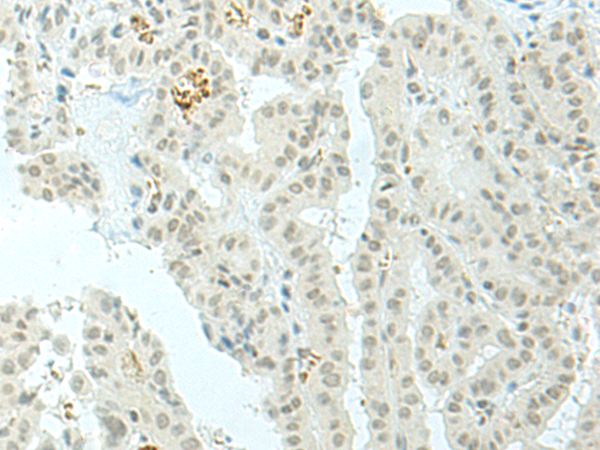

IHC positive control: |

Human lung cancer and Human thyroid cancer |

IHC Recommend dilution: |

30-150 |